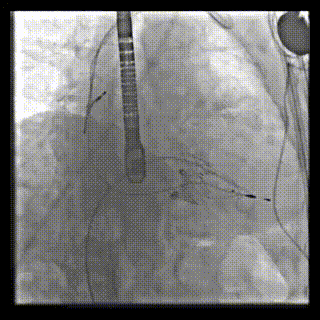

本周三例接受LuX-Valve Plus經血管三尖瓣置換術的患者中,第一例患者為冠狀動脈旁路移植術+Bentall+二尖瓣成形術后;第二例患者為永久起搏器植入術后,存在跨三尖瓣導線;第三例患者合并房顫、房缺及左心耳封堵術后。

三例患者入院后,葛均波院士團隊周達新教授、潘文志教授、張源博士、陳莎莎博士及心超室的潘翠珍教授、李偉教授對患者的情況進行詳細評估和討論,最終決定為三例患者選擇LuX-Valve Plus40mm、50mm和50mm型號的瓣膜進行手術治療。手術后即刻拔除氣管插管,術后患者三尖瓣反流癥狀得到顯著改善,復查心超結果顯示人工三尖瓣瓣膜支架固定穩(wěn)定,瓣葉關閉形態(tài)未見異常,未見明顯反流。